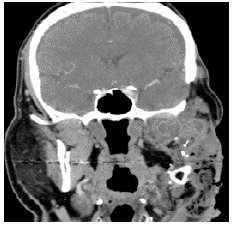

Eleven years after the initial surgery, and after 3 surgeries, a new local relapse was discovered. On physical examination, the patient was found in good condition, with left facial palsy and mass in left masticator space with extension to hard and soft palate, in addition to left submandibular ganglion conglomerate. Contrasted CT showed a mass that involved the left masticator space, lobed, of heterogeneous density with extension towards the skull and average cranial fossa of 36.7x53.6x42mm in anteroposterior section (Figures 3 and 4); biopsy and histopathological study confirmed ameloblastoma.

Source: Document obtained during the study.

Figure 3 Computed tomography of paranasal sinuses with evidence of heterogeneous and hypotensive mass in the left masticator space of lobed contours with dimensions of 36.7x53.6x42.7mm.

Figure 4 Computed tomography of paranasal sinuses showing heterogeneous mass in left masticator space with extension to the base of the skull and middle cranial fossa.